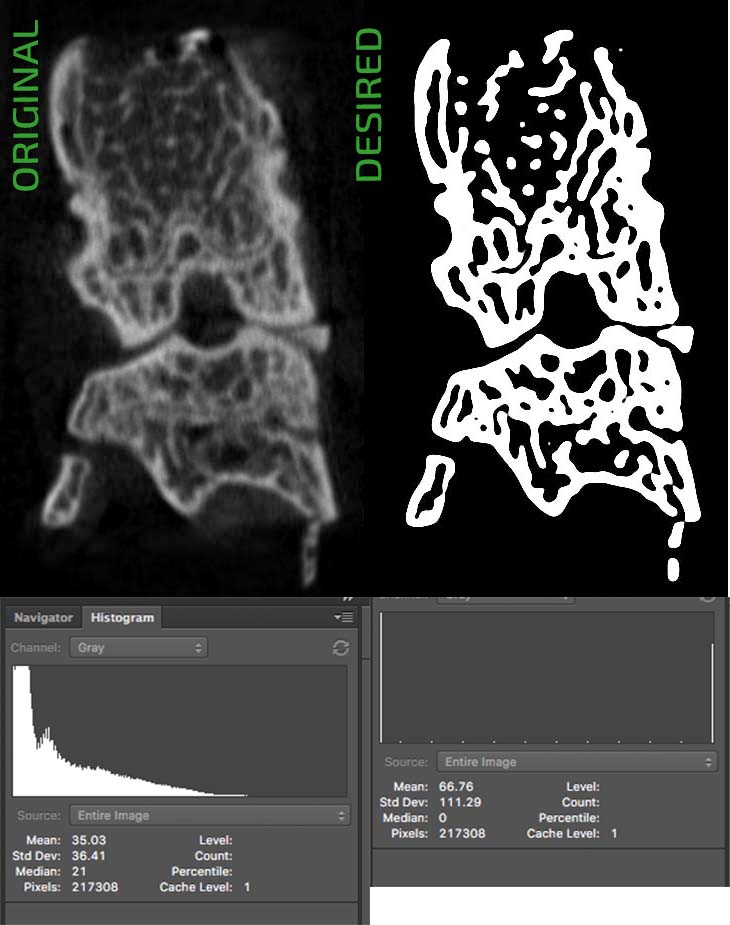

I’m new to OpenCV. I have multiple images. One example image is shown in the upper-left corner of the following figure. Basically I want to separate the background and foreground so that the edges are clear and I can detect the outline correctly.

Finally, when I looked at the Photoshop filter gallery, I noticed a filter called Stamp, which gave me the result I wanted (top right corner). It makes the edges clear and I want to use some blur for soft corners.